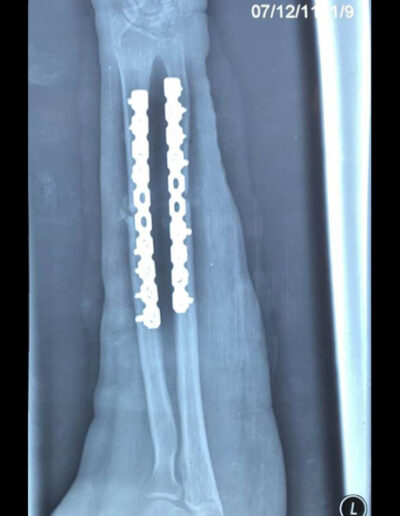

As a positive example, we would like to mention the case of 27-year-old Nabile. Six months ago, the patient suffered a forearm fracture in a car accident, which was treated in another hospital by plating the ulna and radius. Unfortunately, the material was removed far too early, a good five months later. The bone had not yet healed and a nonunion, as we call it, developed in the area of the fracture. This means that the bone at the fracture site does not have stable contact between the individual fragments and is therefore mobile and flexible, like a joint. This caused the young mother considerable pain and severely limited her ability to function as a mother of three small children. She therefore sought our help and came to our consultation hour. We agreed on surgical correction with implantation of bone material in the defect zone, which was taken from the patient's iliac crest during the same operation. We were able to perform the procedure on August 12, 2019. The X-ray now shows correct restoration of the two forearm bones with stabilizing bridging by two plates. After the operation, Céline began exercising the nearby joints through mobilization and provided instruction on self-therapy and correct positioning as part of daily physical therapy. The patient was extremely satisfied and grateful and, with our help, will be able to resume her duties as a mother and housewife. This case encourages us to continue our work here despite difficult conditions and to help people in need.